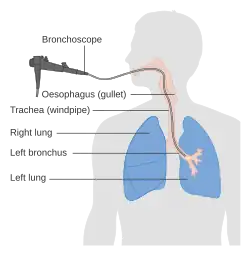

- Bronchoscopy

- According to the American Heart Association, bronchoscopy is a reliable method used to visualize the cause of choking when not resolved via oxygen and supportive care.[23] Bronchoscopy also is a crucial tool in foreign body removal after supportive care has been provided and the person who is choking is stable.[24] However, bronchoscopy is an invasive form of imaging and intervention in comparison to the below diagnostic tools, and requires sedation to perform.[24]

There are many advanced medical treatments available to relieve choking or airway obstruction, including the removal of a foreign object with the help of a laryngoscope or bronchoscope. The use of any commercial approved anti-choking device, if it is available nearby, may be a more abrupt solution, but brief.